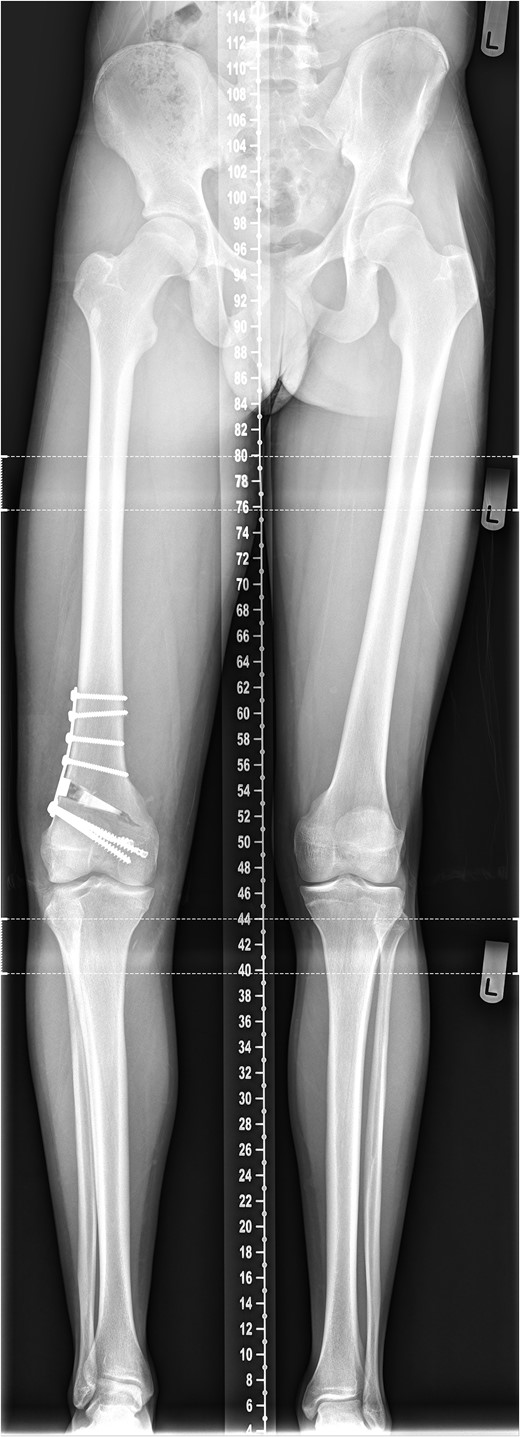

The patient's initial management was non-operative with a period of knee protection with a range of movement brace and intensive rehabilitation. Approximately 3 months after the index injury he returned to competitive football but shortly after his return sustained a further valgus injury and despite further conservative treatment was unable to return to sport. He was referred to our service with ongoing instability symptoms. Upon clinical assessment we noted an asymmetric valgus alignment of the knee and abnormal laxity of the MCL. Radiographic investigations revealed an abnormality of the lateral distal femur and alignment radiographs confirmed the valgus mal-alignment with abnormal opening of the medial tibio-femoral joint space on single-leg stance radiographs (Figs 2–4). We obtained the patient's MRI scan and reviewing this with Radiology colleagues revealed subtle changes of increased lateral femoral physis fluid density on T-2 weighted images consistent with a Salter Harris Type V injury (Fig. 5).

Long-leg alignment radiograph showing valgus deformity of the right knee.